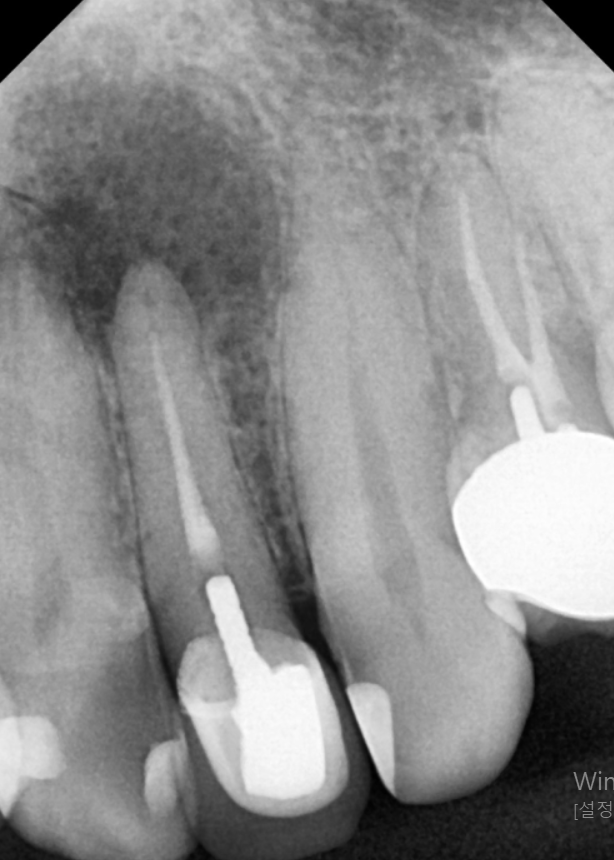

한 달 뒤,

시꺼멓게 보이던 뿌리 끝 염증이

눈에 띄게 사라진 모습!!

260219 / 260324

이제 이 치아가 잘 아물어서 환자분이

다시 편안하게 식사하실 수 있도록

정성껏 마무리해 드릴 일만 남았네요. ^^